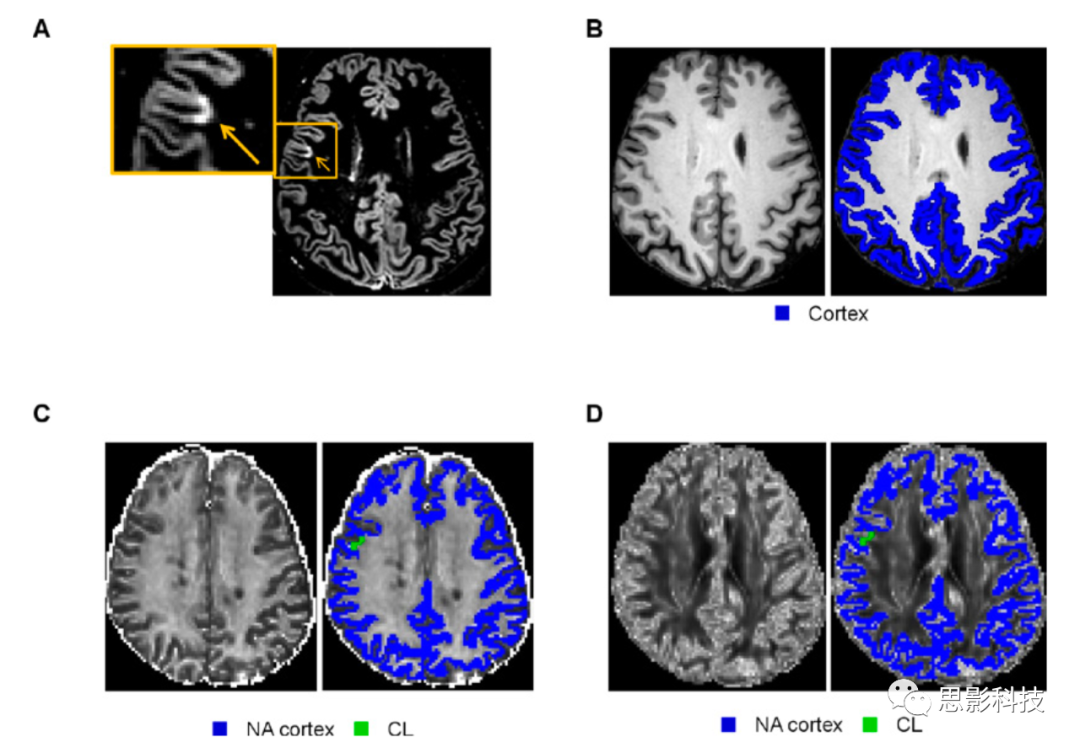

基于已發(fā)表的建議和偽影排除,根據(jù)DIR計(jì)算并量化CLs (1A和補(bǔ)充材料)。由兩個(gè)經(jīng)驗(yàn)豐富的評(píng)分者協(xié)商一致完成在DIR上手動(dòng)檢測(cè)CLs,并使用局部閾值分割技術(shù)估計(jì)CLs (Jim V.8.0 software, www.xinapse.com)。CLs量化僅局限于皮質(zhì)而不累積皮質(zhì)下WM(皮質(zhì)下白質(zhì),即I型、II型和IV)WM/GM混合型病變(I)且皮質(zhì)區(qū)主要延伸(>50%)。

使用FSL SIENAx軟件對(duì)3D-T1加權(quán)圖像進(jìn)行全腦、GM、皮質(zhì)和WM的分割及其歸一化的計(jì)算(1B)。有關(guān)更多詳細(xì)信息,請(qǐng)參閱補(bǔ)充材料。

(A)根據(jù)已發(fā)表的指南(橙色箭頭)DIR序列上識(shí)別CLs

(B)使用FSL SIENAx軟件(藍(lán)色)在矢狀面3D T1加權(quán)序列上分割灰質(zhì)。

(C)NA皮質(zhì)(藍(lán)色)CL(綠色)ICV_f及其量化。

(D)ODI及其在NA (藍(lán)色)CL(綠色)的量化。